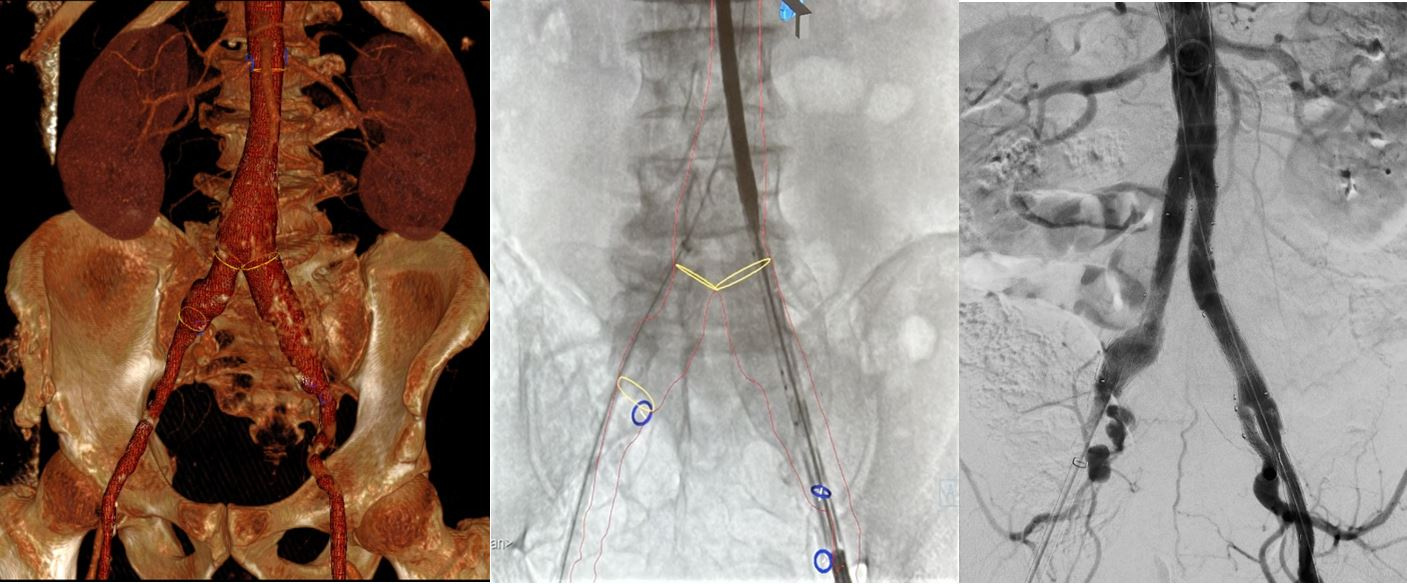

Nový prístroj si našiel okamžité uplatnenie v liečbe komplexných ochorení aorty.

Pacient s výduťou brušnej aorty a panvových tepien ošetrený miniinvazívne cez malý rez v slabine pomocou špeciálnej cievnej protézy, ktorá umožňuje zachovať tok aj do vnútornej panvovej tepny. Pomocou 3D navigácie a fúzie s CT obrazom sa skrátil celkový čas implantácie a výrazne zredukovala radiačná dávka aj objem podanej kontrastnej látky.